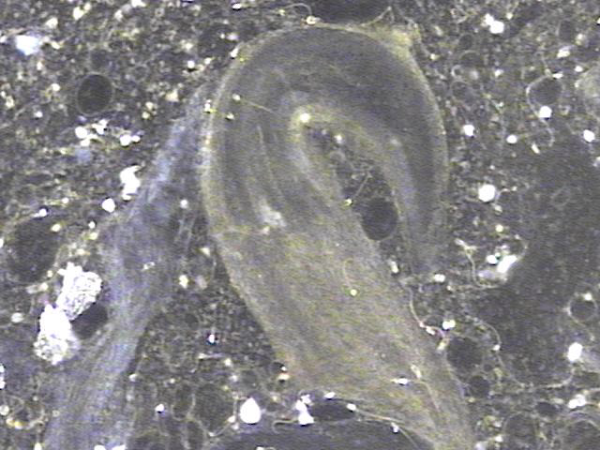

내원당일 전립선의 표적 치료후 배양과 전립선액의 PCR 검사를 위해 채취하고 검사한 현미경학적 확대 사진입니다.

A high-magnification microscopic image taken on the day of the visit, following targeted prostate therapy,

showing the prostatic fluid sample collected for culture and PCR testing.